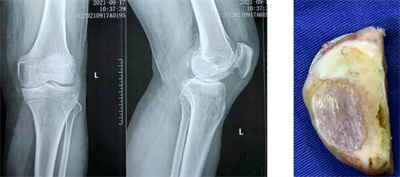

(圖示膝前內(nèi)側(cè)骨關(guān)節(jié)炎X線及術(shù)中情況)